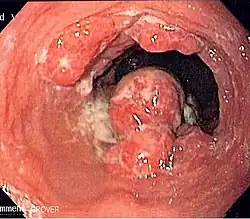

Anatomy

- Length is about 25 cm. Esophageal lesion distance on EGD is typically given from incisors

Presentation

- 50% present with local or locoregional disease.